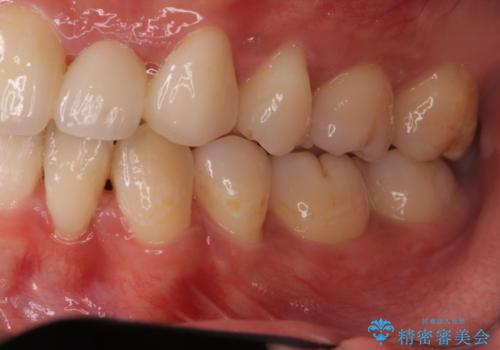

矯正治療で歯並びを治した後、乳歯を抜いたところにブリッジを入れています。

左上の奥歯はすれ違っていたためそのかみ合わせも整えています。

歯を抜いて治療を行ったため、Eラインが整った形で治療ができました。口が断然閉じやすくなっています。